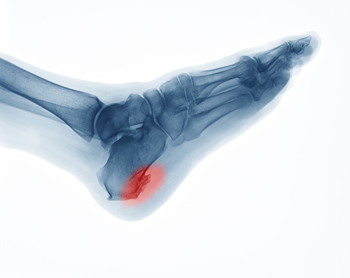

A heel spur is a bony calcium deposit that forms between the heel and the arch of the foot, often causing sharp pain, especially when standing or walking. Bone spurs commonly develop due to repetitive strain on the plantar fascia, which is the ligament that connects the heel to the toes. Risk factors include obesity, flat feet, high arches, poor footwear, and activities that place excessive stress on the feet, such as running or prolonged standing. Symptoms may include heel pain, inflammation, and difficulty walking comfortably. A podiatrist can diagnose heel spurs through examination and imaging, provide custom orthotics, recommend stretching and strengthening exercises, and discuss treatment options to relieve pain and restore mobility. If you have heel pain, it is suggested that you consult a podiatrist who can accurately diagnose what may be going on.

Heel spurs are formed by calcium deposits on the back of the foot where the heel is. This can also be caused by small fragments of bone breaking off one section of the foot, attaching onto the back of the foot. Heel spurs can also be bone growth on the back of the foot and may grow in the direction of the arch of the foot.